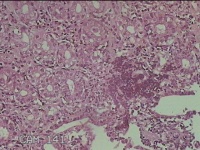

胃角粘膜

性别

男

年龄

29岁

临床诊断

复合性溃疡;慢性胃炎

一般病史

上腹部疼痛1个月余。

标本名称

大体所见

灰白粉红色组织小米大2团。

良性病变。